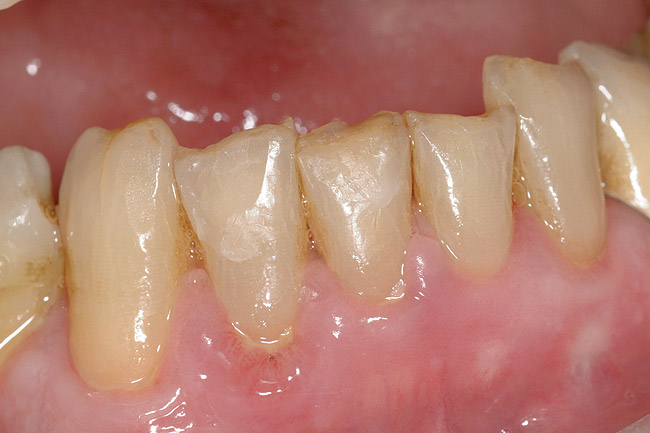

Figure  6  Erosion and abrasion in a xerostomic patient with Sjögren’s syndrome.

Figure 6

In salivary hypofunction, the lack or decrease of saliva increases the friction and effectiveness of the abrasivity of toothpaste and toothbrushing. The site-specific tooth surface loss reflects the normal protective role of serous saliva and salivary pellicle in a site-specific manner.26 Also, involuntary regurgitation and chronic regurgitation such as in hiatal hernia and gastroesophageal reflux disease (GERD) negatively affect the oral cavity because the refluxate (intrinsic acid) is low in pH (pH < 2) and readily dissolves the tooth minerals. Dental erosion can be considered an atypical manifestation of GERD. Voluntary regurgitation in cases of anorexia nervosa and bulimia also introduces gastric refluxate into the oral cavity and causes degradation of the dental structures.27-31 Additionally, various medications with anti-cholinergic side effects (eg, psychiatric, antihypertensive, a combination of medications, etc) cause salivary hypofunction. The chronic use of medications that are low in pH (liquid, chewable tablets, or inhaler forms) has a detrimental effect on teeth and can potentially cause erosion.